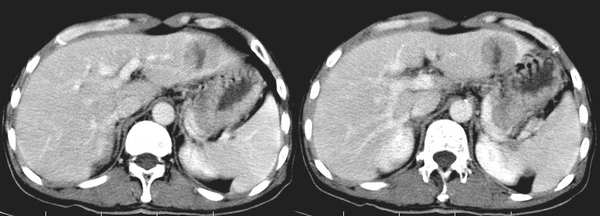

标题: CT2110:肝左叶占位

男59岁

增强扫描病灶中央见裂隙状低密度影,支持局灶性结节状增生[emb6]

fnh:动脉期明显强化,静脉期呈等密度,平衡期呈低密度.应该算是典型表现.